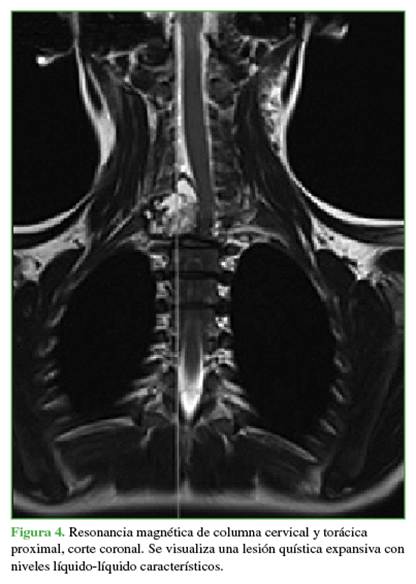

Los estudios complementarios mostraron un compromiso vertebral extenso: en C7 (arco posterior), zonas 4-7 y niveles III y IV de la clasificación de Weinstein-Boriani-Biagini; en T1 (cuerpo vertebral), zonas 10-3 y niveles III y IV; en T2 (pedículo derecho más arco posterior), zonas 3-7, niveles III y IV.11 Las lesiones eran de tipo quística expansiva (Figuras 3 y 4). Ante el patrón expansivo de la lesión, se descartó la sospecha de un hemangioma vertebral. Se interpretó el caso como una lesión con diagnóstico presuntivo de QOA grado 3 de Enneking.

El plan terapéutico consistió en disminuir el riesgo de sangrado, descomprimir la lesión y estabilizar.